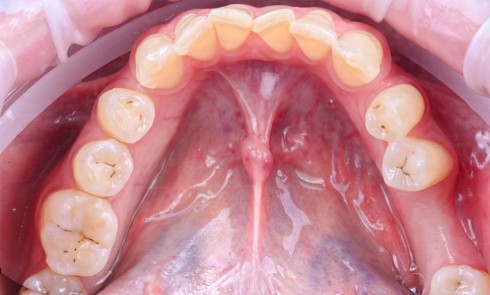

Enfant de 9 ans dont une incisive centrale maxillaire a été expulsée en jouant au football. Appel immédiat de la mère à qui l’on conseille de conserver la dent expulsée dans du sérum physiologique (fig. 1). Le temps extra-alvéolaire à sec a été inférieur à 5 minutes. Le patient arrive 40 minutes après le traumatisme dans l’Unité d’Odontologie pédiatrique. Après interrogatoire, examen clinique et radiographique, un rinçage de l’alvéole est effectué et la dent est réimplantée le plus rapidement possible (fig. 2). Une contention semi-rigide est ensuite placée (fig. 2). La dent étant mature, la prise en charge endodontique (séance de Ca(OH)2 puis obturation à la gutta percha) débute deux semaines plus tard (fig. 3 et 4) afin de limiter les risques d’infection, de résorption. Le suivi sur quatre années montre une dent fonctionnelle, sans ankylose ni résorption radiculaire ou osseuse.

Adolescente de 17 ans ayant trois dents (12, 11, 21) expulsées lors de travaux aux champs (fig. 5), ainsi qu’une luxation latérale de la 13. Elle est adressée par les urgences du CHU de Rennes et la consultation a lieu 6 heures…